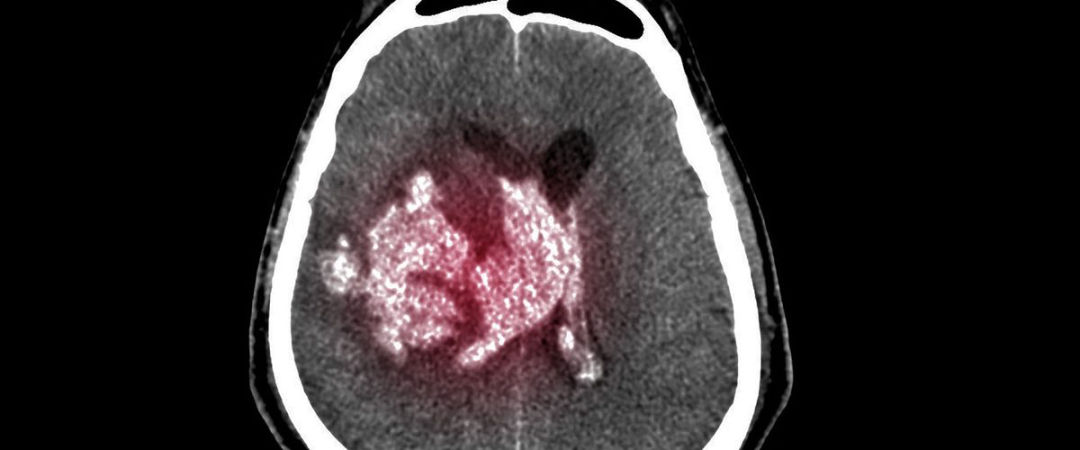

Derrame subdural

Es una acumulación de sangre entre la cubierta del cerebro (duramadre) y la superficie del cerebro.

Un hematoma subdural es a menudo el resultado de un traumatismo craneal grave. Este tipo de hematoma subdural se encuentra entre el más letal de todos los traumatismos craneales. El sangrado llena la zona cerebral rápidamente, comprimiendo el tejido cerebral. Esto a menudo ocasiona traumatismo craneal y puede llevar a la muerte.

Con cualquier hematoma subdural, las pequeñas venas que están entre la superficie del cerebro y su cubierta externa (la duramadre) se estiran y se rompen, permitiendo que la sangre se acumule. En adultos mayores, las venas a menudo ya se han estirado debido al encogimiento cerebral (atrofia) y se lesionan más fácilmente.